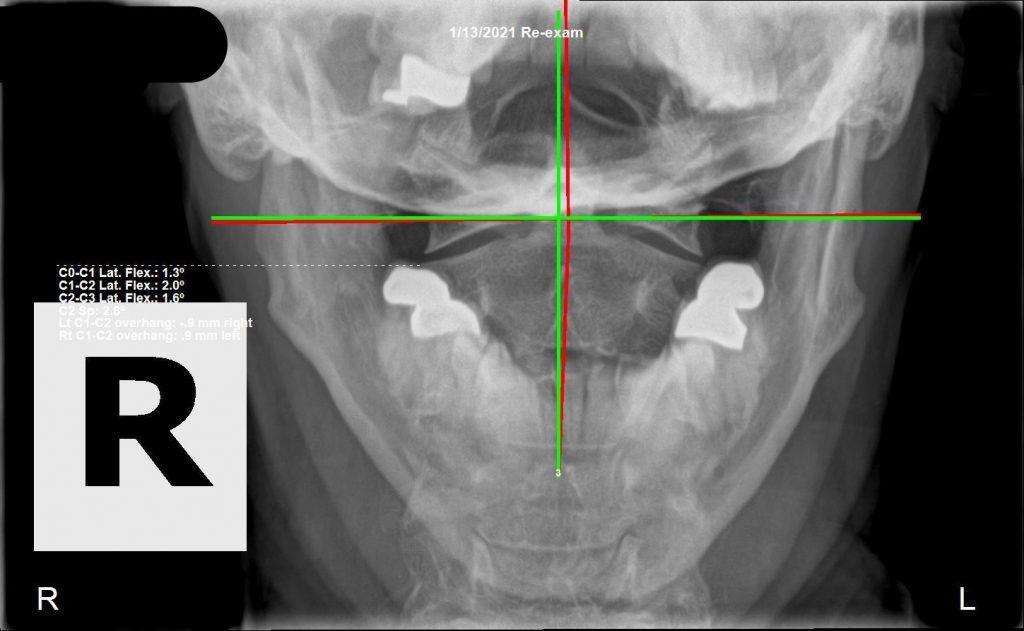

Before and after spinal X-ray comparison — subluxation based care care Royal Palm Beach

Unlike symptom-based care, we analyze for nerve system function through spinal alignment, and adjust only if necessary, only where necessary. This specificity is not only what sets us apart from other chiropractic offices — it's what produces the results we achieve. The eye-opening look on a patient's face when they see their X-rays change significantly, and feel the corresponding change in function, never gets old.